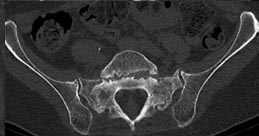

73 year old woman with osteoporosis who fell and fractured her pelvis. She was unable to walk and developed lumbopelvic dissociation (seperation of the spine from the pelvis and lower half of the body) from an unstable sacral fracture and displacement.

Lumbopelvic fixation with prophylactic cement augmentation and patient was immediately able to walk again.